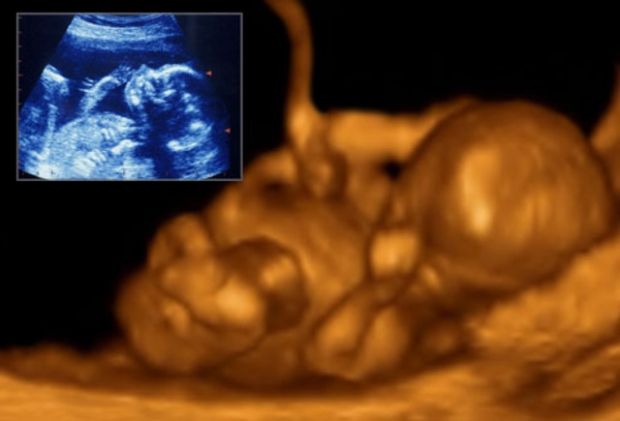

УЗИ (ультразвуковое исследование) — важный инструмент для наблюдения за развитием беременности, позволяющий родителям увидеть малыша на разных этапах. В статье представлены фото УЗИ по неделям беременности, что поможет понять изменения в ребенке и обсудить ключевые моменты с врачом. Эти изображения визуализируют развитие плода и предоставляют информацию о его здоровье, что делает их незаменимыми для будущих мам и пап.

Врачи подчеркивают важность ультразвукового исследования на разных этапах беременности. УЗИ позволяет не только подтвердить факт беременности, но и отслеживать развитие плода, выявлять возможные аномалии и оценивать состояние матери. Специалисты отмечают, что каждое исследование имеет свои особенности в зависимости от срока. На ранних сроках УЗИ помогает увидеть сердцебиение и определить количество эмбрионов. Позже, на более поздних сроках, врачи могут оценить анатомию плода, его размеры и положение в матке. Фотографии, полученные во время УЗИ, становятся важной частью медицинской документации и часто вызывают эмоциональный отклик у родителей. Врачи рекомендуют проходить УЗИ в установленные сроки, чтобы обеспечить здоровье как матери, так и ребенка.